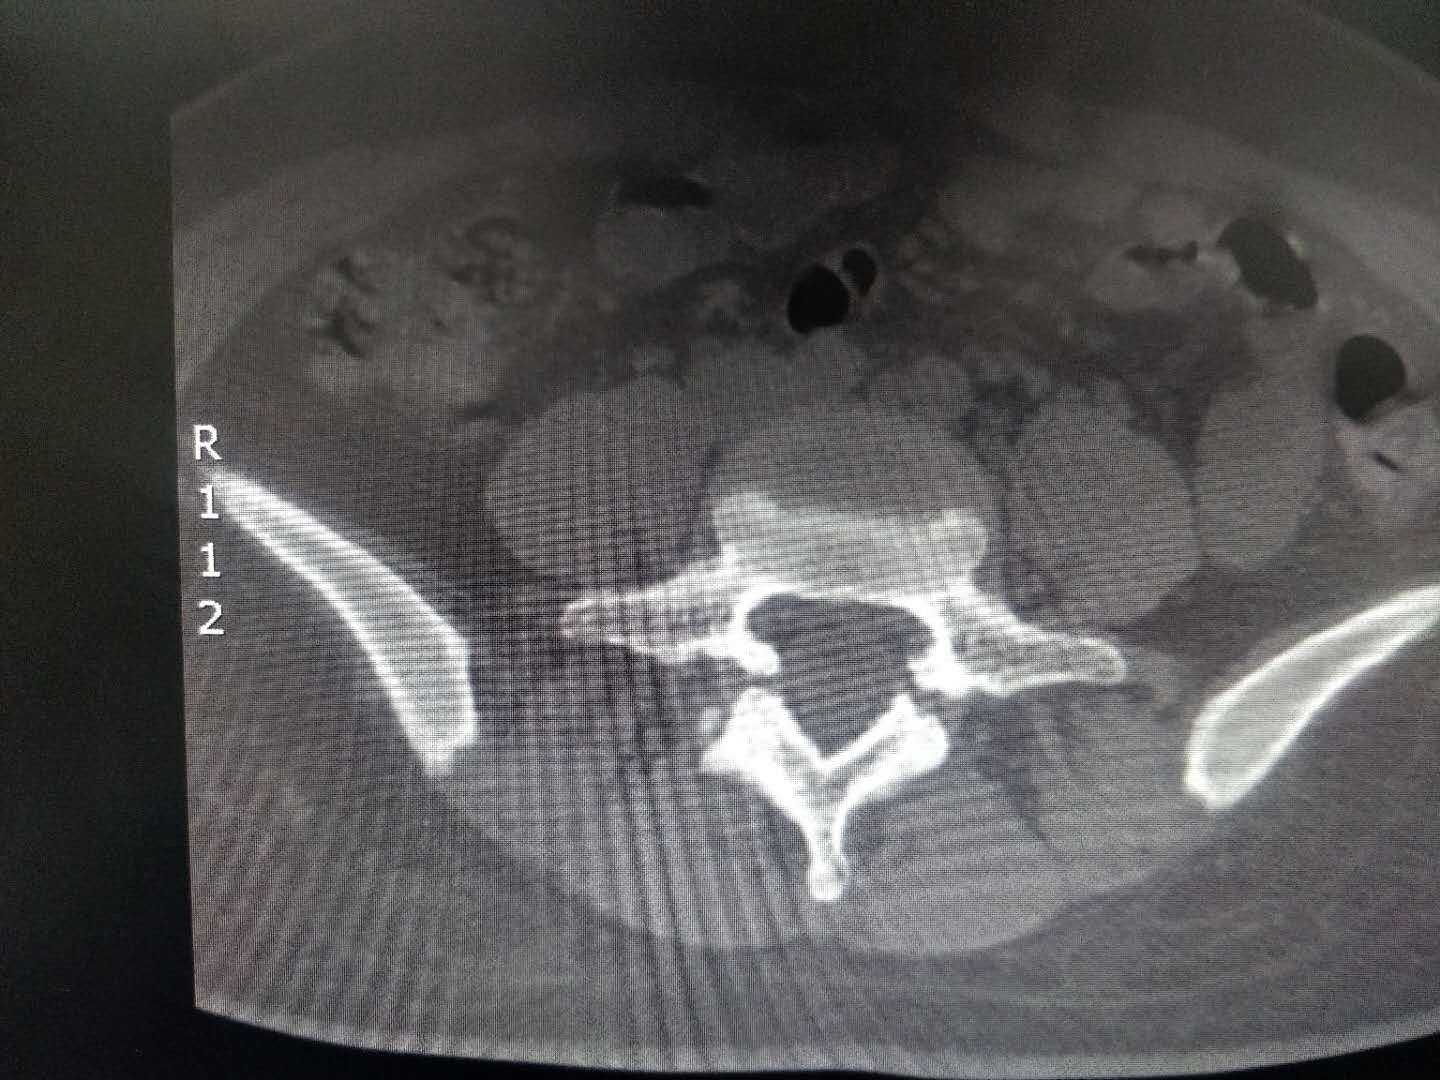

ct显示腰5双侧峡部裂,相应节段椎管狭窄.

l5双侧峡部裂影像求助